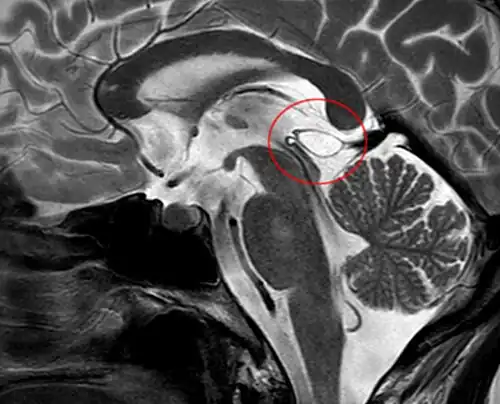

Another case: sagittal